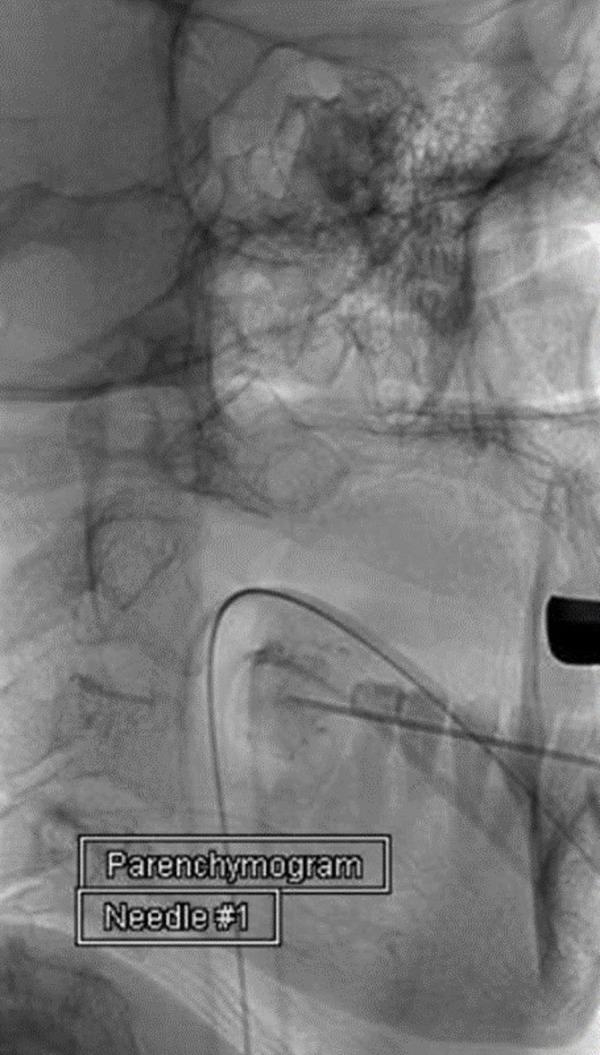

Preoperative embolization via transarterial route is an acceptable adjunct to the treatment of carotid body tumors (CBT). Direct tumor puncture for embolization has been previously described as a safe and feasible option. We revisit this technique and present our initial experience treating CBT via direct puncture. We identified six patients that underwent preoperative embolization of CBT using a direct puncture technique embolized with Onyx (EV3 Micro Therapeutics Inc., Irvine, CA, USA). After defining the angioarchitecture via digital subtraction angiography, the tumor was targeted with Onyx. Using a 21-gauge needle, the tumor was punctured using a fluoroscopic road mask. There were no immediate post-procedural complications following embolization. All patients underwent definitive resection within 24 hours. During surgery, the embolization material did not affect surgical maneuvers. In addition, the estimated blood loss was noted to average 50 ml.  Although early in our experience, direct percutaneous embolization of CBT appears to be a reproducible and well-tolerated endovascular treatment option. Overall, the reported body of evidence available confirms the safety and efficacy of direct intralesional embolization with Onyx.

经动脉途径的术前栓塞是治疗颈动脉体瘤(CBT)的一种可接受的辅助方法。先前已描述直接肿瘤穿刺栓塞是一种安全可行的选择。我们重新审视了这项技术,并介绍了我们通过直接穿刺治疗CBT的初步经验。我们确定了6例使用直接穿刺技术并用Onyx(美国加利福尼亚州欧文市EV3 Micro Therapeutics公司)栓塞进行CBT术前栓塞的患者。通过数字减影血管造影确定血管结构后,用Onyx对肿瘤进行靶向栓塞。使用21号针,在荧光透视路图引导下穿刺肿瘤。栓塞后无即刻术后并发症。所有患者均在24小时内接受了根治性切除。手术过程中,栓塞材料未影响手术操作。此外,估计平均失血量为50毫升。尽管这只是我们的初步经验,但CBT的直接经皮栓塞似乎是一种可重复且耐受性良好的血管内治疗选择。总体而言,现有报道的证据证实了使用Onyx进行直接瘤内栓塞的安全性和有效性。